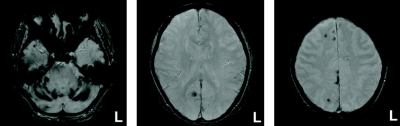

検査所見 : 血液所見:赤血球 450 万、Hb 14.0 g/dL、Ht 42 %、白血球 5,600、血小板 30万。血液生化学所見:総蛋白 7.8 g/dL、アルブミン 4.0 g/dL、総ビリルビン 1.0 mg/dL、AST 16 U/L、ALT 18 U/L、LD 210 U/L (基準 120〜245) 、ALP 250 U/L (基準 115〜359)、γ-GT 18 U/L (基準 8〜50)、CK 80 U/L (基準 30〜140)、尿素窒素 20 mg/d、クレアチニン 0.9 mg/dL、尿酸 5.0 mg/dL、血糖 88 mg/dL、トリグリセリド 150 mg/dL、HDL コレステロール 40 mg/dL、LDL コレステロール 140 mg/dL、Na 145 mEq/L、K 4.0 mEq/L、Cl 104 mEq/L。CRP 0.1 mg/dL。頭部 MRI の T2*強調水平断像を別に示す。